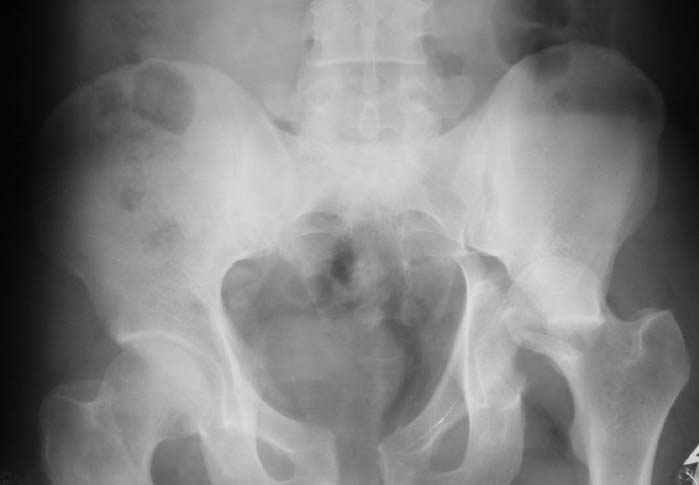

Уважаемый Антон, у Вашего больного имеется транстектальный поперечный перелом вертлужной впадины с переломом заднего края, перелом заднего типа, подвздошный вывих, возможна импрессия и повреждение нерва. Головка при этих повреждениях в нагружаемой части должна быть целой.

Высылаю нечто подобное, аппарат пусть не смущает, просто больного оперировал через 2 месяца после травмы, а у него еще полный разрыв кп сочленения с контрлатеральной стороны.